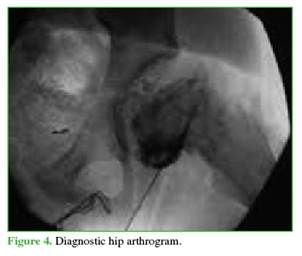

Puncture-aspiration was performed under anesthesia to assess the degree of epiphyseal displacement1 and to evacuate the joint hematoma.2 Then, using a small amount of contrast medium, an arthrogram was performed, which confirmed the displacement and its instability. Magnetic resonance imaging is another modality to reach the diagnosis when instability is suspected; however, an MRI scanner should be available near or within the operating room to perform it during the same anesthetic procedure (Figures 4 and 5).